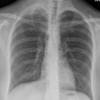

lymphoma

Rt supraclavicular nodes (NHL)

Date: 06/08/2016

Views: 3428